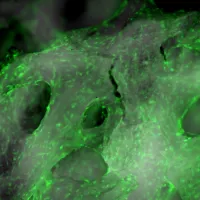

Image galleries

Explore the high-quality images and videos we produce.

Southampton Imaging

Imaging has become an essential part of scientific research, from biomedical sciences to engineering to optoelectronics.